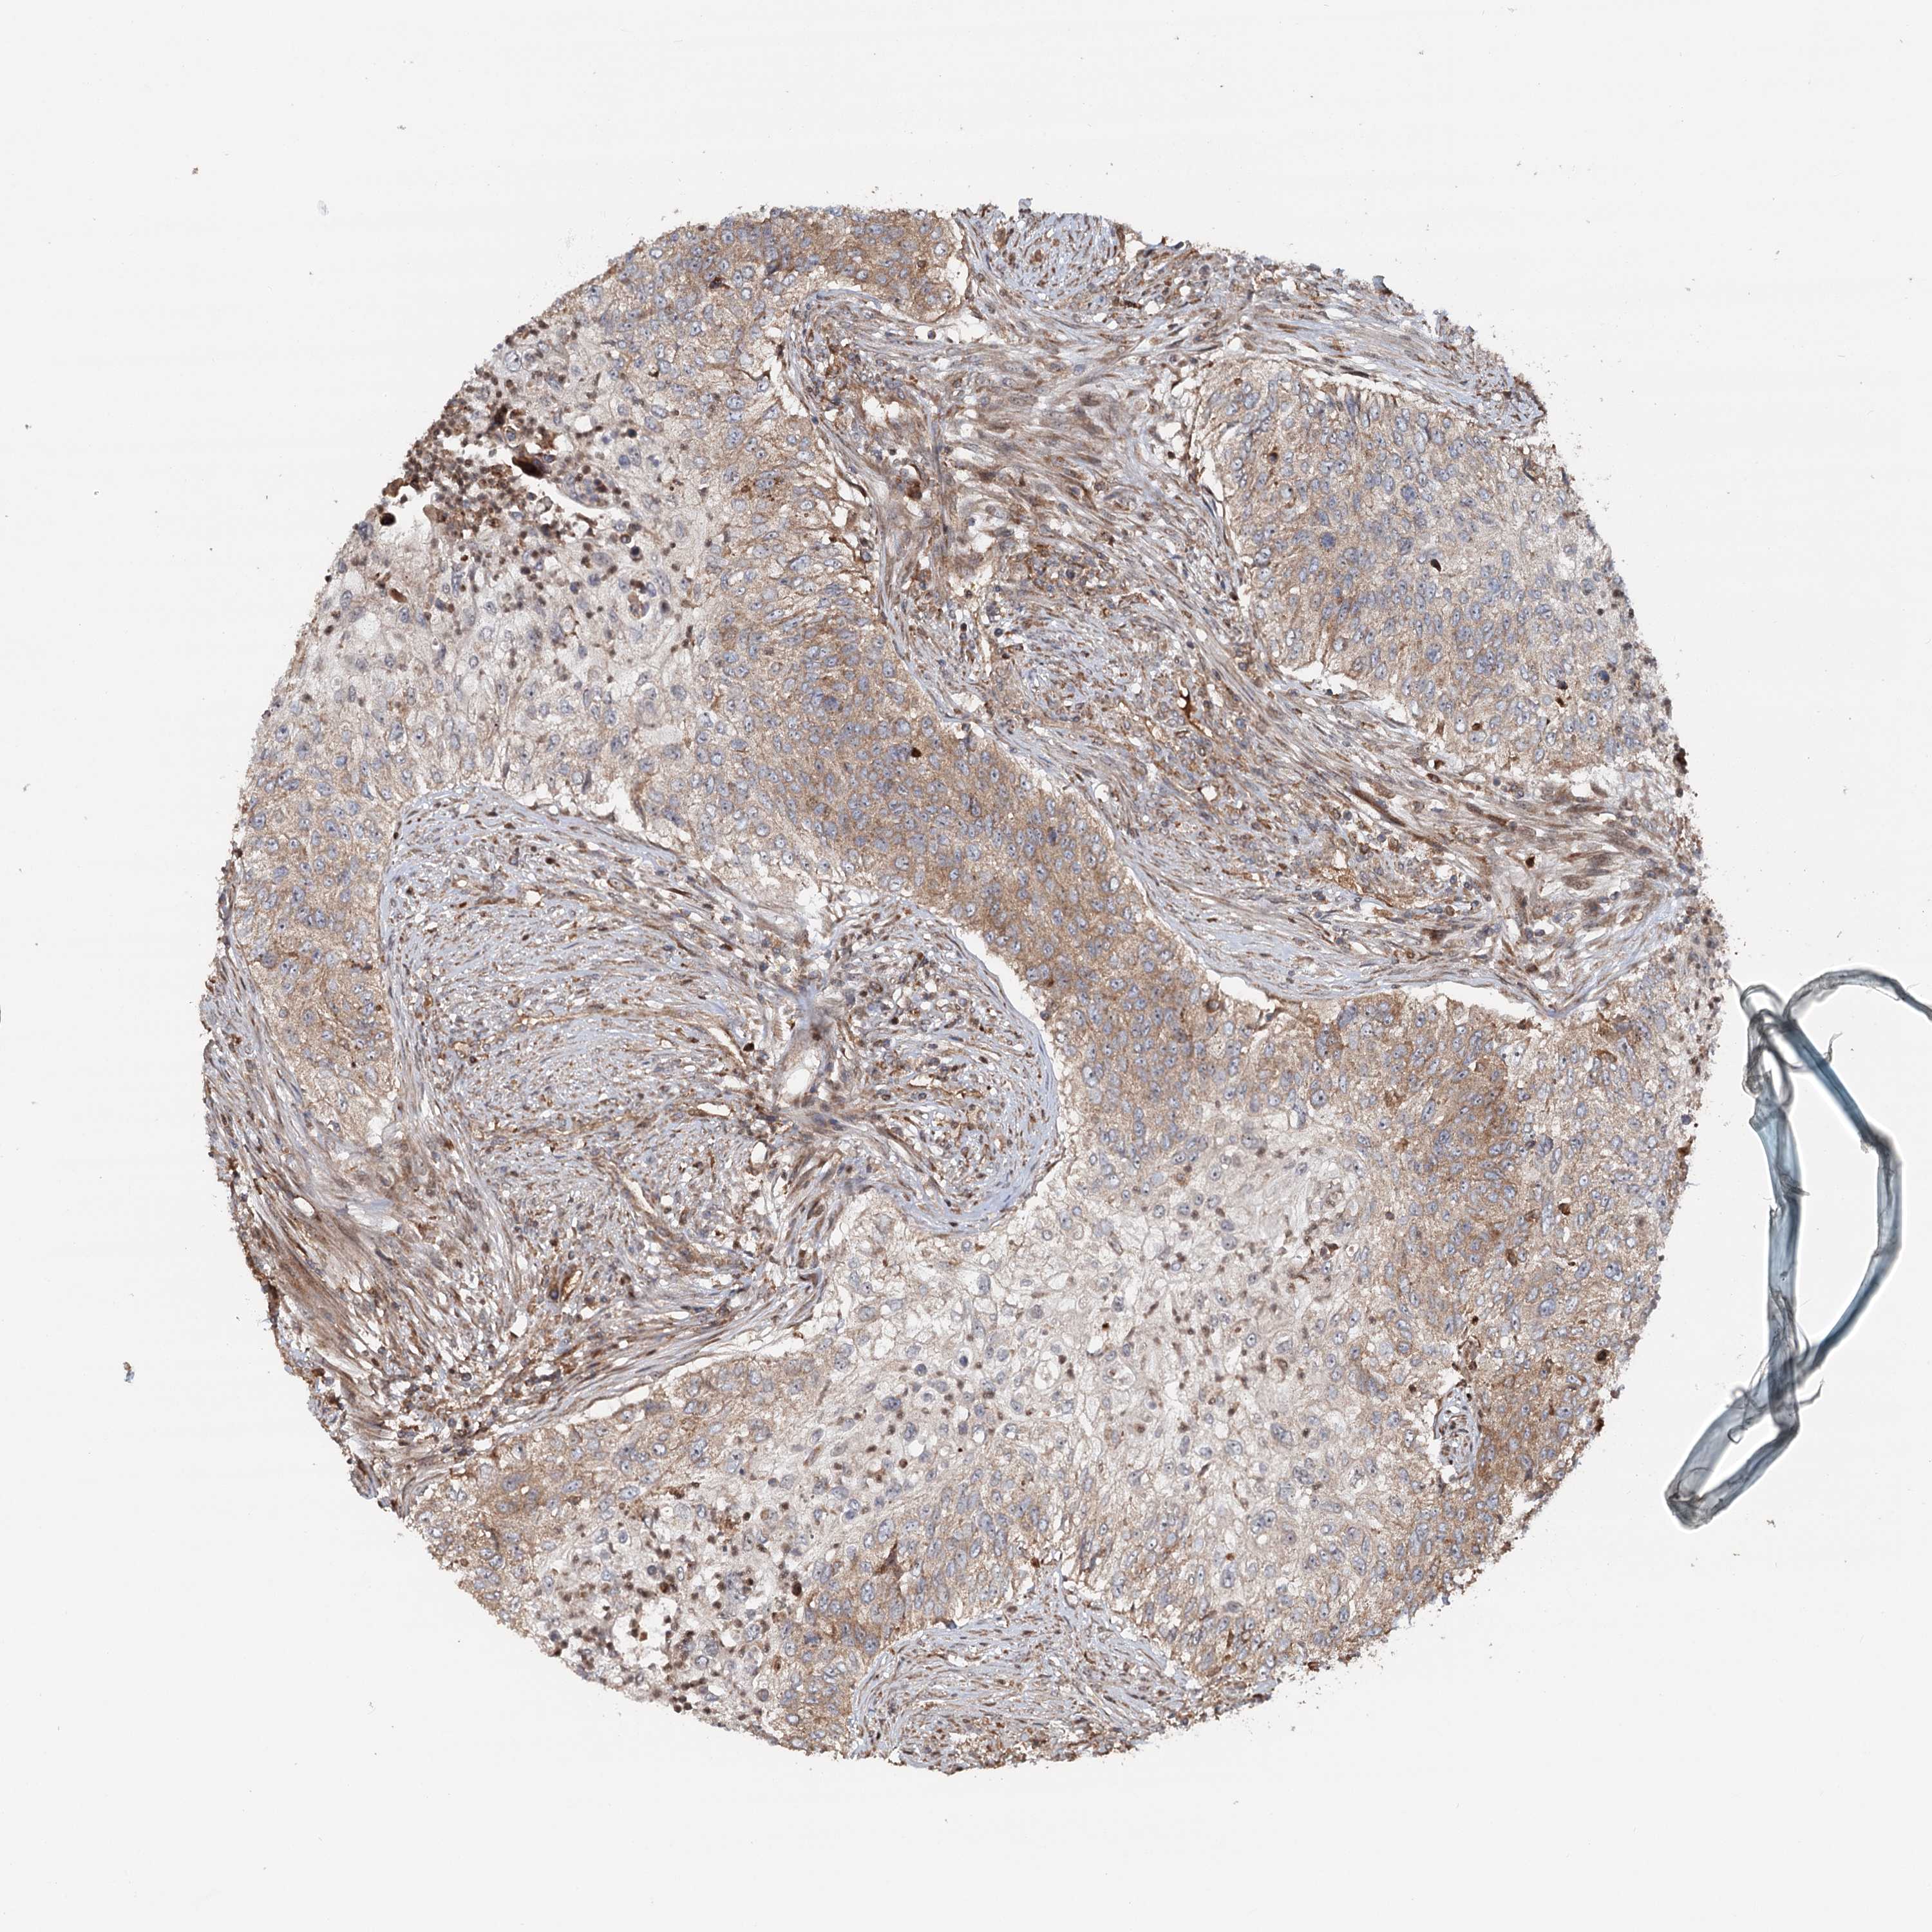

UROTHELIAL CANCER - Protein expressioni

A mouse-over function shows sample information and annotation data. Click on an image to view it in a full screen mode. Samples can be filtered based on level of antibody staining by selecting one or several of the following categories: high, medium, low and not detected. The assay and annotation is described here.

Note that samples used for immunohistochemistry by the Human Protein Atlas do not correspond to samples in the TCGA dataset.

Antibody stainingi

Antibody staining in the annotated cell types in the current human tissue is reported as not detected, low, medium, or high, based on conventional immunohistochemistry profiling in selected tissues. This score is based on the combination of the staining intensity and fraction of stained cells.

Each image is clickable and will lead to virtual microscopy that enables deeper exploration of all samples and also displays staining intensity scores, fraction scores and subcellular localization as well as patient and tissue information for each sample.

Antibody HPA038576

Antibody HPA038577

Staining

High

Medium

Low

Not detected

Intensity

Strong

Moderate

Weak

Negative

Quantity

>75%

75%-25%

<25%

None

Location

Nuclear

Cytoplasmic/membranous

Cytoplasmic/membranous,nuclear

Urothelial carcinoma, High grade

Urothelial carcinoma, Low grade

Urothelial carcinoma, NOS